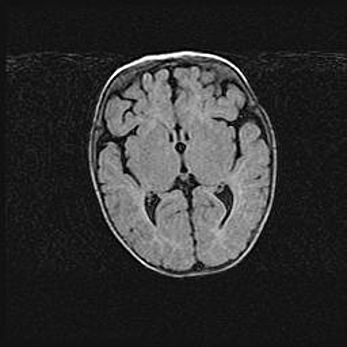

Сообщающаяся гидроцефалия. Кистозная энцефаломаляция головного мозга.

Возраст: 3 месяца 4 дня

Вес: 3100 г

Пол: женский

Окружность головы: 34 см

Срок гестации: 31 неделя

Кистозная энцефаломаляция головного мозга - одна из форм поражения головного мозга в детском возрасте. Характеризуется возникновением множественных и распространённых кист в коре, белом веществе и подкорковых образованиях головного мозга у плодов, новорождённых и детей раннего возраста. Развитие кистозной энцефаломаляции связано с внутриутробной асфиксией и гипотонией, родовой травмой, тромбозом синусов, пороками развития сосудов, инфекциями, сепсисом и другими причинами. Наиболее значимые инфекционные агенты: вирусы простого герпеса, цитомегалии, краснухи, токсоплазмы, энтеробактерии, золотистый стафилококк и другие.